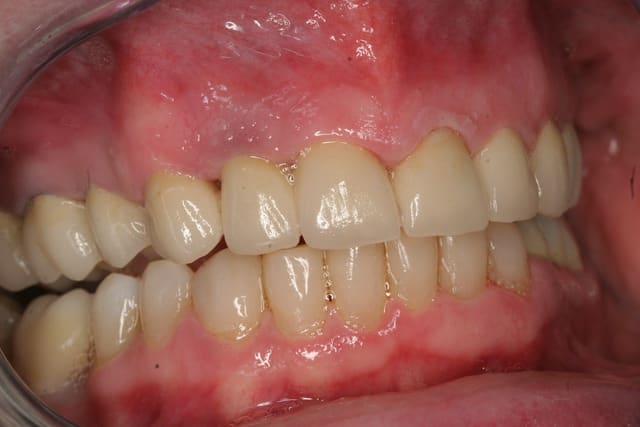

Et voila la pose , pour les habitants du nouveau monde c'est très coloré, pour les Franchouillard c'est naturel... perso je m'en fout la patiente est toute joilleuse et j'ai pas honte de moi, j'ferais encore mieux dés qu'on m'en donneras l'occasion.

Fin 002 j3hb61 - Eugenol

Fin 005 htq1ba - Eugenol

Fin 006 dpgjbp - Eugenol

Fin 008 owjdyz - Eugenol

Fin 007 lhlszz - Eugenol